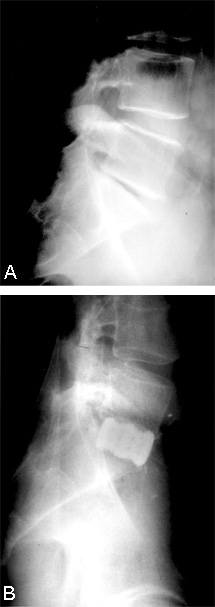

After the implants and grafts are inserted, their final position is assessed endoscopically and radiographically (Figs. 17 and 18). The implants are recessed from the anterior and posterior margins of the disc space. The surgical site is inspected and hemostasis is obtained.